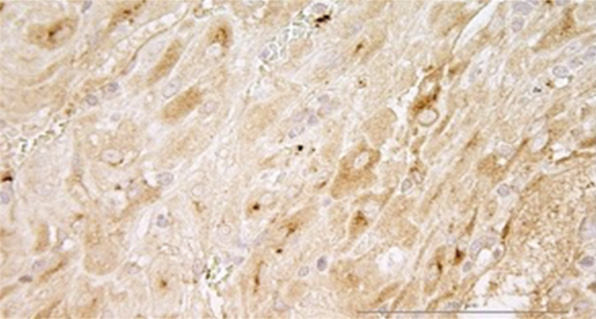

По данным гистологического исследования диагноз «плацентарная адгезивно-инвазивная патология» подтвержден в 100 % случаев (n = 5). При этом микроскопически среди гипертрофированных мышечных волокон визуализированы ворсины хориона с отеком стромы, гиперваскуляризацией и неравномерным полнокровием, а также базальная пластина с эктазией просветов и неравномерно полнокровными сосудами, очаговым некрозом, расслаивающими кровоизлияниями, избыточным количеством фибриноида (рис. 2, а, b).

Рис. 2. Микрофотографии биоптатов миометрия из маточно-плацентарной области: a — ворсина хориона в биоптате миометрия при плацентарной адгезивно-инвазивной патологии (PAS 3a–c); b — децидуальная оболочка в биоптате миометрия при плацентарной адгезивно-инвазивной патологии (PAS 3a–c); c — фрагмент миометрия группы сравнения с полнокровием капиллярного русла из области прикрепления плаценты; d — фрагмент миометрия группы сравнения с участком децидуальной ткани из области прикрепления плаценты; e, f — фрагмент миометрия контрольной группы с участком децидуальной ткани. Окраска гематоксилином и эозином, увеличение ×200